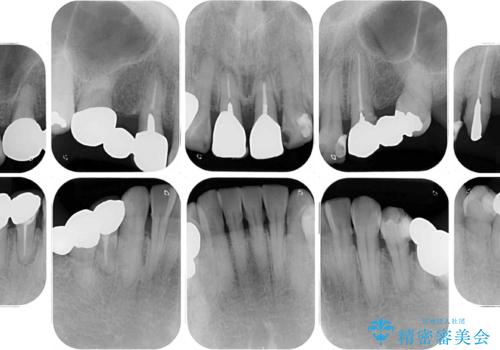

- 歯茎からの出血、入れ歯、歯の欠損、デコボコの前歯などを気にして来院された患者様です。

大の歯科治療嫌いとのことでしたが、今回の治療を契機にしっかりと治療を行いたいとのことでした。

まずは抜歯が必要な歯を抜歯した上で仮歯に置き換え、インプラント埋入や歯周外科処置、根管治療を行うこととしました。

歯肉の状態が落ち着いた後に下顎の矯正治療を行い、その後補綴治療を行うこととしました。